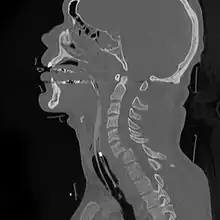

| A fracture of the base of the dens (a part of C2) as seen on CT | |